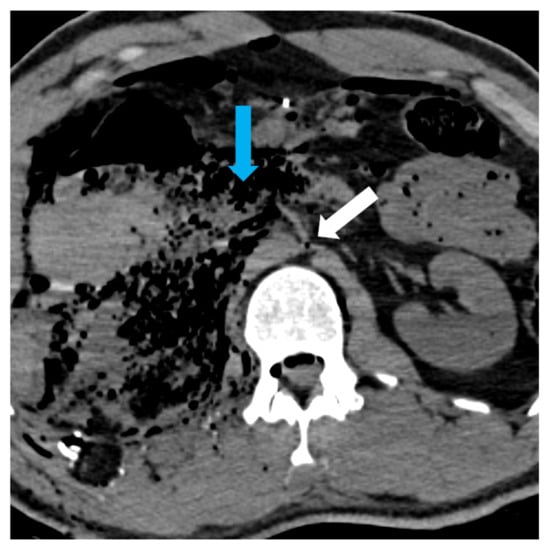

Injuries of the inferior vena cava were very few in number, which may have led to the lack of agreement. (Figure 4).

Figure 4. IVC not visible under hepatic, in emphysematous changes (blue arrow). Abdominal aorta collapsed with the birth of the Superior Mesenteric Artery (white arrow).